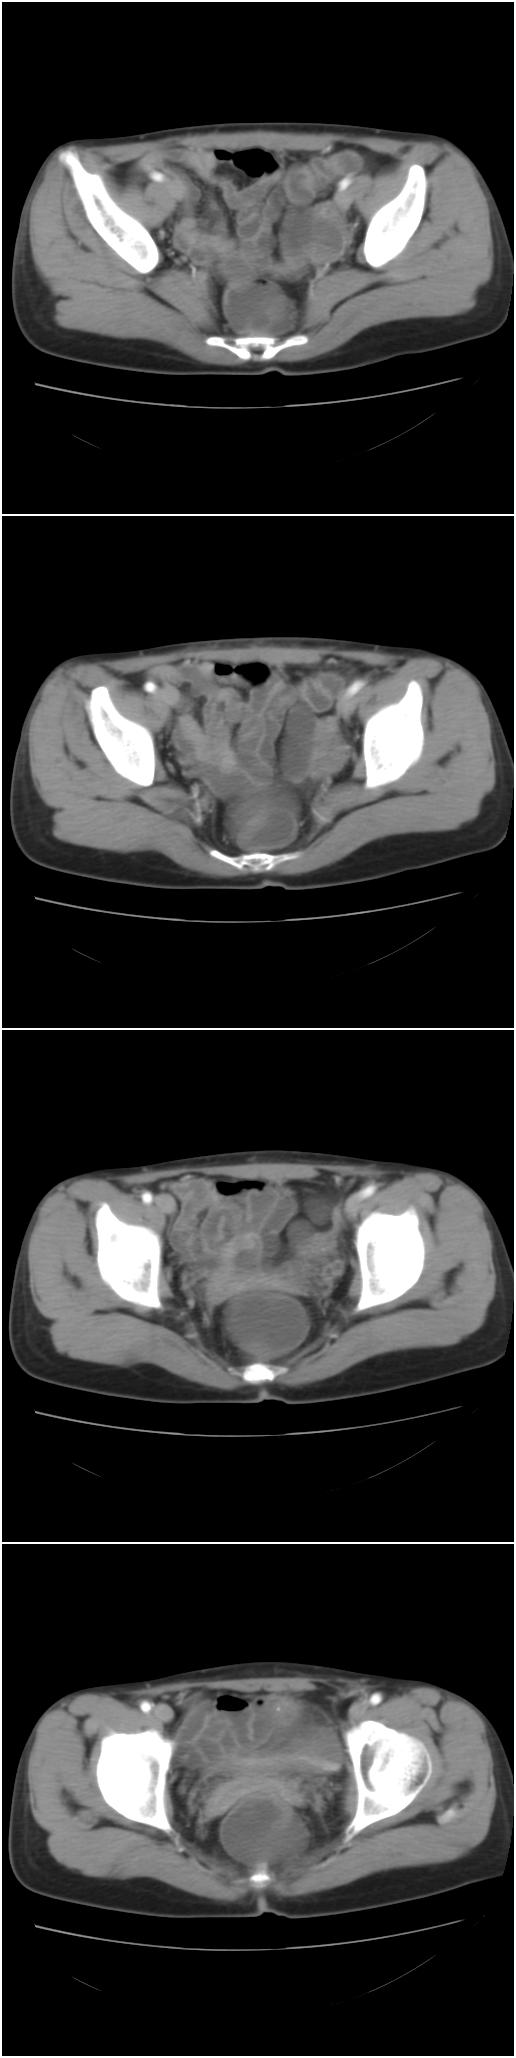

以下是今天的增强片,大家可以看看:

右侧髂骨膨胀性骨质破坏区 囊内密度尚均匀 骨巨细胞瘤可能性大 动脉瘤样骨囊肿不除外 建议mr观察囊内成分明确诊断 左侧附件区包裹性积液

右侧髂后上棘局限性囊状骨质破坏,大部分界清,似见轻度硬化边,内无分格及钙化,病灶上部局部显示模糊。考虑;骨巨细胞瘤可能大,不除外abc。另可见子宫肌瘤术后子宫缺如。

临床和影像学表现:女性患者46岁,有子宫肌瘤手术病史。影像所见可见残余宫颈部分,左右附件未见新生物;右髂骨翼后端囊状膨胀性骨破坏,囊性部分感觉有强化(楼主标上增强前后的ct值就很好了),未见明确的液—液平面,周边硬化不明显或轻度硬化。

分析:患者年龄46岁,没有明确外伤病史,病变呈膨胀性骨破坏,囊性部分未见明确的液—液平面,周边硬化不明显。综合分析该病例比较符合骨巨细胞瘤,不太符合动脉瘤样骨囊肿。

诊断:1、首先考虑骨巨细胞瘤;2子宫肌瘤术后改变